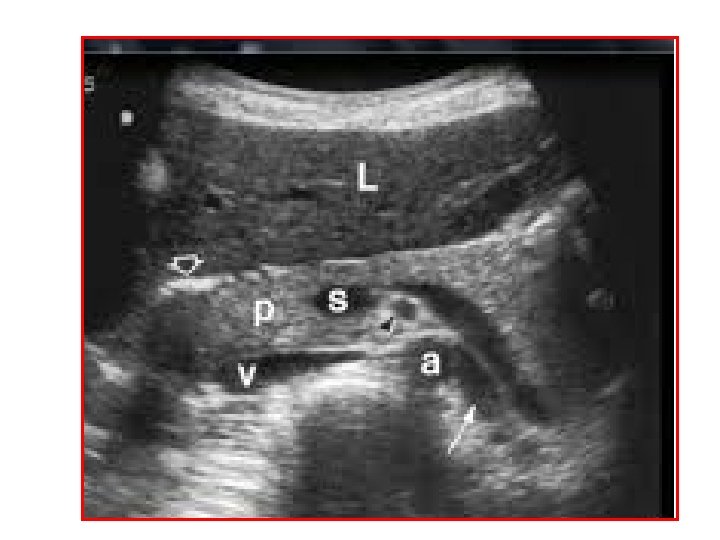

Coupe sur le creux épigastrique PANCREAS : Morphologie, Taille, Echostructure Repères vasculaires: vasculaires Veine splénique et Artère mésentétique

1 - Sinus rénal 2 - cortex 3 -foie gauche